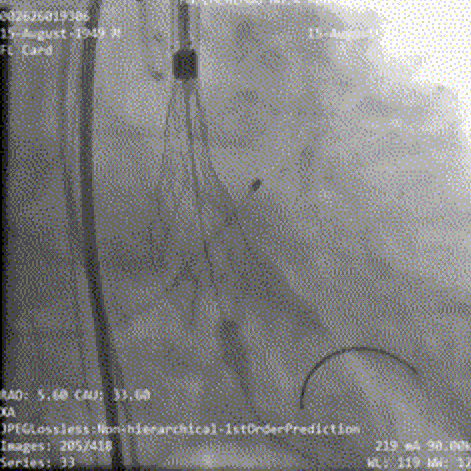

术前行冠状动脉造影提示左右冠状动脉未见有意义狭窄;

左冠造影

右冠造影